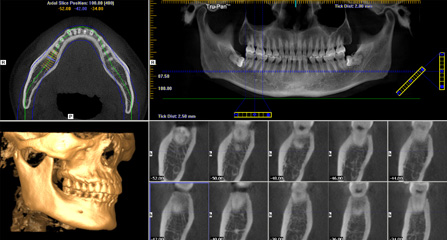

三维影像数据 一次性精确采集